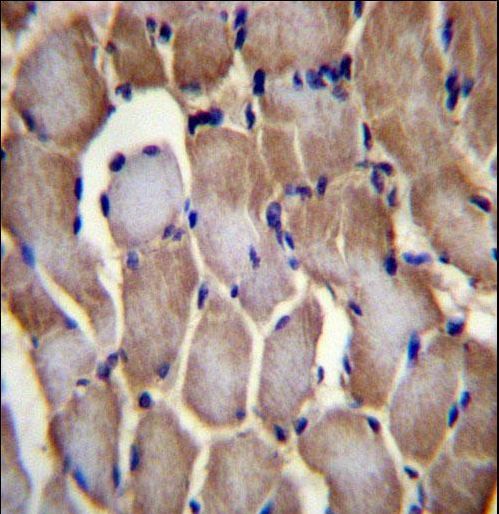

- Submitted by

- LSBio (provider)

- Enhanced method

- Genetic validation

- Experimental details

- SEPN1 Antibody immunohistochemistry of formalin-fixed and paraffin-embedded human skeletal muscle followed by peroxidase-conjugated secondary antibody and DAB staining.